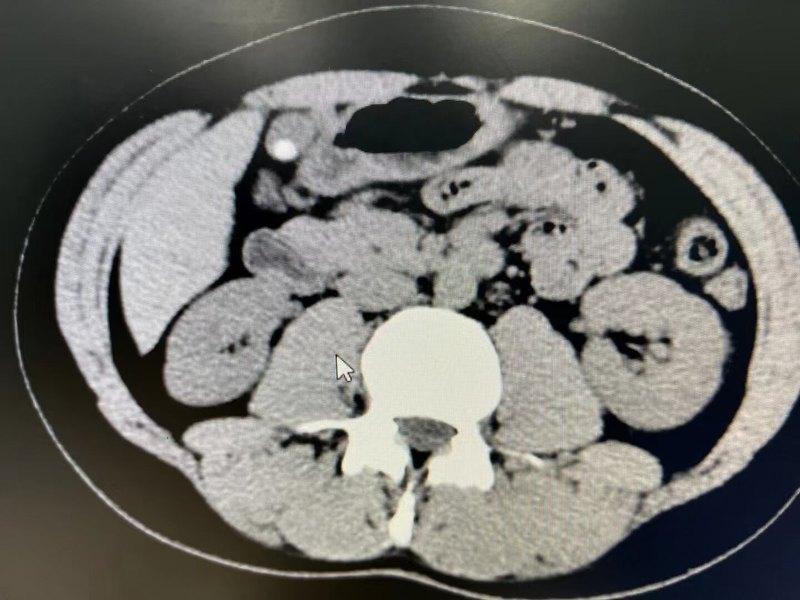

文章轉(zhuǎn)載自:都市女報(bào) 山東省立三院(山東省消化病醫(yī)院)肝膽外科張锎主任談膽總管結(jié)石治療 女報(bào)記者 孫墨琦 通訊員 馮延民 很多膽結(jié)石的患者,都應(yīng)有過這樣的感受,上腹絞痛難忍,難以進(jìn)食惡心,想著只要能把石頭拿出來,剖腹也能接受。但是傳統(tǒng)的開腹手術(shù),留給患者的傷害是長(zhǎng)久的而且會(huì)在肚皮上留下明顯的刀口。這一來,雖然病治了,但也付出了極大的代價(jià)。后來,隨著微創(chuàng)手術(shù)的發(fā)展,長(zhǎng)長(zhǎng)的疤痕被鑰匙孔大小的創(chuàng)口所替代,這使得很多結(jié)石患者看到了希望。 最近,記者在山東省立三院(山東省消化病醫(yī)院)肝膽外科發(fā)現(xiàn),對(duì)膽道內(nèi)的結(jié)石,可以從口中進(jìn)入。張锎主任介紹,這種經(jīng)口的取石方式,叫作ERCP技術(shù),中文全稱叫經(jīng)內(nèi)鏡胰膽管造影,目前已發(fā)展成為膽胰疾病的主要治療技術(shù)之一。這項(xiàng)技術(shù)能使很多備受結(jié)石折磨而又不能開刀的患者擺脫病痛煎熬。 不通則痛 結(jié)石體質(zhì)容易復(fù)發(fā)結(jié)石 家住萊蕪的趙大娘,今年已經(jīng)80歲了,年輕的時(shí)候有過膽囊結(jié)石,就把膽囊切除了,隨后一直也沒有復(fù)發(fā),但是最近總是感覺腹部絞痛,疼起來的時(shí)候,滿頭虛汗腹痛難忍,也無法進(jìn)食還總愛惡心,到當(dāng)?shù)蒯t(yī)院一查才知道是膽總管結(jié)石,但是礙于趙大娘高齡并且伴有高血壓、心臟病,無法進(jìn)行手術(shù),醫(yī)生只能規(guī)勸患者疼的時(shí)候打消炎藥緩解,這樣下來趙大娘撐了近半年,后來聽說山東省立三院(山東省消化病醫(yī)院)不開刀就能取出結(jié)石,腹痛實(shí)在不能忍受就來到了山東省立三院(山東省消化病醫(yī)院)。張主任根據(jù)患者癥狀,一句這病能治,寬了趙大娘的心,立刻安排ERCP手術(shù),在麻醉下實(shí)施,不到20分鐘就取出了結(jié)石,術(shù)后5天便康復(fù)出院,折(了半年的結(jié)石就這么順利而又神奇的解決了。 張锎主任介紹,像趙大娘一樣的患者并不少見,自身體質(zhì)、環(huán)境的影響,造成“結(jié)石體質(zhì)”容易復(fù)發(fā)結(jié)石,膽囊結(jié)石雖已治療,但又在膽總管復(fù)發(fā),這一類都是我們平常所說的膽結(jié)石。根據(jù)近年來醫(yī)院接診的患者來看,膽總管結(jié)石患者逐漸增加。膽總管結(jié)石就是指位于膽總管內(nèi)的結(jié)石,大多數(shù)為膽色素結(jié)石或以膽色素為主的混合結(jié)石,好發(fā)于膽總管下端。中醫(yī)講“不通則痛”,因?yàn)榻Y(jié)石堵塞了膽汁的正?!斑\(yùn)行”,才會(huì)導(dǎo)致患者腹痛?!皬膶?duì)身體的危害、癥狀的嚴(yán)重性、治療的困難等方面來講,膽總管結(jié)石比膽囊結(jié)石要嚴(yán)重得多?!睆堉魅翁嵝眩坏┙?jīng)B超或其他方法證實(shí)患了膽總管結(jié)石,不管有多少,哪怕只有一個(gè),也不管它有多大,不管處于靜止期還是活動(dòng)期,都應(yīng)爭(zhēng)取及早去醫(yī)院積極治療,因?yàn)榻Y(jié)石就像“定時(shí)炸彈”,一旦堵住膽總管,就會(huì)發(fā)生膽管炎,如形成急性化膿性膽管炎,病情況十分危急,病死率較高。而且患有膽結(jié)石的患者,大多也是結(jié)石體質(zhì),哪怕手術(shù)清理干凈,也有30%的復(fù)發(fā)率。所以患有結(jié)石要盡快處理。 那么哪些人屬于“結(jié)石體質(zhì)”?張主任介紹可分為下列幾類人群: 第一種是已經(jīng)有很長(zhǎng)時(shí)間的膽道病史,并且發(fā)作時(shí)伴有寒戰(zhàn)發(fā)熱、黃疸的急性膽管炎,這些人比較易患結(jié)石,所以平常一定要注意通過飲食預(yù)防; 第二種是年齡在30-50歲之間以及老年人,處于這個(gè)年齡段的患者需要特別關(guān)注自己的身體,在飲食上一定要多加注意; 第三種是長(zhǎng)期飲食無規(guī)律者,經(jīng)常不吃早餐的人或是晚餐吃得較晚的人容易患上結(jié)石; 第四種事飲食過于單一,愛吃肉類、動(dòng)物內(nèi)臟的人,還有愛吃辛辣、多鹽、多糖食物的人,這些人容易誘發(fā)結(jié)石。 結(jié)石患者不耐受不適宜手術(shù)一樣治療 一般手術(shù)會(huì)有相應(yīng)的禁忌癥,這會(huì)讓一些不符合條件的患者,只好忍受劇痛而不能從根上解決病患。膽總管結(jié)石就是如此。對(duì)于一些年長(zhǎng)并伴有嚴(yán)重心肺腦合并癥的患者,由于其無法耐受麻醉而無法進(jìn)行手術(shù),另外還有一些曾經(jīng)做過開腹手術(shù)的患者,由于其腹腔內(nèi)存在黏連,無法分清臟器故也不適宜進(jìn)行手術(shù)。一般這一類患者,只能靠注射消炎藥止痛,這使很多肝膽外科專家深感無奈。 既然傳統(tǒng)的外科開刀窺探腹腔內(nèi)狀況的方式行不通,不如就進(jìn)到膽道內(nèi),從里面治療結(jié)石。由此醫(yī)院的結(jié)石治療開始了研究轉(zhuǎn)型:從開腹手術(shù)、腹腔鏡手術(shù)轉(zhuǎn)換為經(jīng)口內(nèi)窺鏡的治療方式,即從內(nèi)查找排除結(jié)石,也就是如今醫(yī)院開展的ERCP技術(shù),它就是經(jīng)口內(nèi)鏡下直接在膽管內(nèi)找尋結(jié)石并取出來。這種方式與我們了解的胃鏡有相似之處:胃鏡是內(nèi)窺鏡到達(dá)胃部,而膽總管取石則是經(jīng)過胃部、幽門到達(dá)十二指腸,在膽道開口處精細(xì)操作,將膽道內(nèi)的結(jié)石取出放至腸道內(nèi)。通過這種小切口的方式,很多不耐受不適宜手術(shù)的患者最后能夠進(jìn)行治療。 “醫(yī)院經(jīng)常接診一些80歲以上的高齡膽總管患者,他們往往會(huì)伴有一些心腦血管的基礎(chǔ)疾病,常規(guī)的手術(shù)方式不適宜,可是通過ERCP技術(shù),就可以進(jìn)行取石?!睆堉魅握f,目前科室開展的微創(chuàng)治療方式分為兩類,一類為腹腔鏡手術(shù),而另一大分支就是ERCP技術(shù),這種技術(shù)是國(guó)內(nèi)外公認(rèn)為是膽總管結(jié)石首選的治療方式。 張主任為記者演練了手術(shù)的過程。手術(shù)是通過應(yīng)用一種特殊的切開刀,將十二指腸內(nèi)與膽管相連的膽管開口切開擴(kuò)大,再插入取石網(wǎng)籃,到存在有結(jié)石的膽總管內(nèi),將結(jié)石套住后拖至十二指腸內(nèi),結(jié)石就可以隨大便自體排出體外。至今團(tuán)隊(duì)已完成超16000余例ERCP,為山東省首家ERCP過萬例的醫(yī)院,全國(guó)范圍內(nèi)亦名列前茅。目前,肝膽外科團(tuán)隊(duì)整合各種內(nèi)鏡微創(chuàng)技術(shù),以“病人為中心”、以“療效為中心”,為病人提供最合理的治療方案。 延伸鏈接 膽石癥患者飲食指南 益: 1、要多食含維生素C的各種新鮮水果,如鮮橙等。維生素C可以使體內(nèi)多余的膽固醇轉(zhuǎn)變?yōu)槟懼?,使得分解脂肪的膽汁減少與膽固醇的中和,進(jìn)而降低聚集形成膽結(jié)石的機(jī)會(huì)。 2、要多吃含維生素A的食物,如綠色菜蔬、胡蘿卜、番茄、白菜等。維生素A對(duì)上皮細(xì)胞具有滋潤(rùn)營(yíng)養(yǎng)的作用,這可以減少膽固醇結(jié)石的形成。 3、要多吃瘦肉、雞、魚、核桃、黑木耳、海帶、紫菜等,要用植物油炒菜,而且所吃的菜要以燉、燴、蒸為主。 4、應(yīng)進(jìn)食低脂肪、低膽固醇食品,如噴鼻菇、木耳、芹菜、芽菜、海帶、藕、魚肉、兔肉、雞肉、鮮豆類等。 忌: 1.忌吃高膽固醇食物,如動(dòng)物心、肝、腦、腸、蛋黃、松花蛋、魚子、巧克力等。 2.忌吃高脂肪食物,如肥肉、油炸食品、蛋糕、點(diǎn)心、油條等。 3.忌暴飲暴食?!?4.忌辛辣刺激調(diào)味品,如辣椒、花椒粉、咖哩粉等。 5.忌煙、酒、咖啡,避免其刺激膽道括約肌,使膽道括約肌痙攣,從而導(dǎo)致膽汁排出困難。 專家介紹 張锎,主任醫(yī)師,山東省消化病醫(yī)院副院長(zhǎng),山東省立第三醫(yī)院肝膽外科主任。 從事肝膽外科專業(yè)27年,熟練掌握十二指腸鏡、膽道鏡、IDUS、SpyGalss等內(nèi)鏡微創(chuàng)技術(shù),尤其擅長(zhǎng)經(jīng)口內(nèi)鏡不開刀微創(chuàng)治療膽總管結(jié)石(ERCP+EST),膽管良、惡性狹窄的內(nèi)鏡診斷,以及膽胰腫瘤的姑息性膽道內(nèi)支架引流術(shù)等。 帶領(lǐng)內(nèi)鏡微創(chuàng)團(tuán)隊(duì)在全國(guó)及全省率先開展十余項(xiàng)ERCP相關(guān)技術(shù),并于2014年在全省率先突破萬例ERCP手術(shù),目前擔(dān)任兩項(xiàng)國(guó)家級(jí)臨床操作技術(shù)ERCP培訓(xùn)基地負(fù)責(zé)人,被收錄2018年胡潤(rùn)“中國(guó)好醫(yī)生”榜單。榮獲2020年度“人民好醫(yī)生”。 社會(huì)任職: 中國(guó)醫(yī)師協(xié)會(huì)ERCP醫(yī)師培訓(xùn)中心主任 中國(guó)ERCP技術(shù)標(biāo)準(zhǔn)化人才培訓(xùn)基地主任 中國(guó)中西醫(yī)結(jié)合學(xué)會(huì)消化內(nèi)鏡分會(huì)ERCP專家委員會(huì)副主任委員 中國(guó)醫(yī)師協(xié)會(huì)胰腺病專業(yè)委員會(huì)委員 中華醫(yī)學(xué)會(huì)消化內(nèi)鏡學(xué)分會(huì)內(nèi)鏡外科學(xué)組委員 中國(guó)醫(yī)師協(xié)會(huì)內(nèi)鏡醫(yī)師分會(huì)腹腔鏡內(nèi)鏡外科專業(yè)委員會(huì)委員 中國(guó)醫(yī)師協(xié)會(huì)內(nèi)鏡醫(yī)師分會(huì)內(nèi)鏡診療質(zhì)控專業(yè)委員會(huì)委員 中國(guó)外科內(nèi)鏡醫(yī)師聯(lián)盟高級(jí)會(huì)員 世界內(nèi)鏡醫(yī)師協(xié)會(huì)膽胰管內(nèi)鏡中國(guó)協(xié)會(huì)山東省分會(huì)常務(wù)副會(huì)長(zhǎng) 山東省外科ERCP醫(yī)師聯(lián)盟主任委員 山東省醫(yī)學(xué)會(huì)消化介入學(xué)分會(huì)副主任委員 山東省醫(yī)師協(xié)會(huì)肝膽胰腔鏡微創(chuàng)醫(yī)師分會(huì)常務(wù)委員 山東省中西醫(yī)結(jié)合學(xué)會(huì)消化內(nèi)鏡分會(huì)副主任委員 山東省研究性醫(yī)院協(xié)會(huì)膽道微創(chuàng)外科分會(huì)副主任委員 山東省醫(yī)師協(xié)會(huì)重癥感染醫(yī)師分會(huì)委員兼腹腔感染學(xué)組組長(zhǎng) 坐診時(shí)間:周一上午

臨床肝囊腫根據(jù)生長(zhǎng)部位和大小不同,處理辦法不同,具體如下: 1、可以經(jīng)B超引導(dǎo)下對(duì)于深部位囊腫,即處于肝實(shí)質(zhì)內(nèi)部的囊腫進(jìn)行治療。如果囊腫較小,可以進(jìn)行經(jīng)皮經(jīng)肝穿刺治療。穿刺以后抽出清亮囊液,證明和膽管不相通。通過注射無水酒精破壞黏膜,導(dǎo)致無囊液分泌,囊腫可以緩慢閉死; 2、如果囊腫較大,可以通過腹腔鏡肝囊腫開窗引流術(shù)使分泌的囊液直接流到腹腔內(nèi)部,不會(huì)對(duì)正常肝產(chǎn)生壓迫作用; 3、極少數(shù)靠近邊稍部位的肝囊腫,例如左肝外葉較大囊腫,可以通過腹腔鏡囊腫切除術(shù)達(dá)到臨床治愈目的。